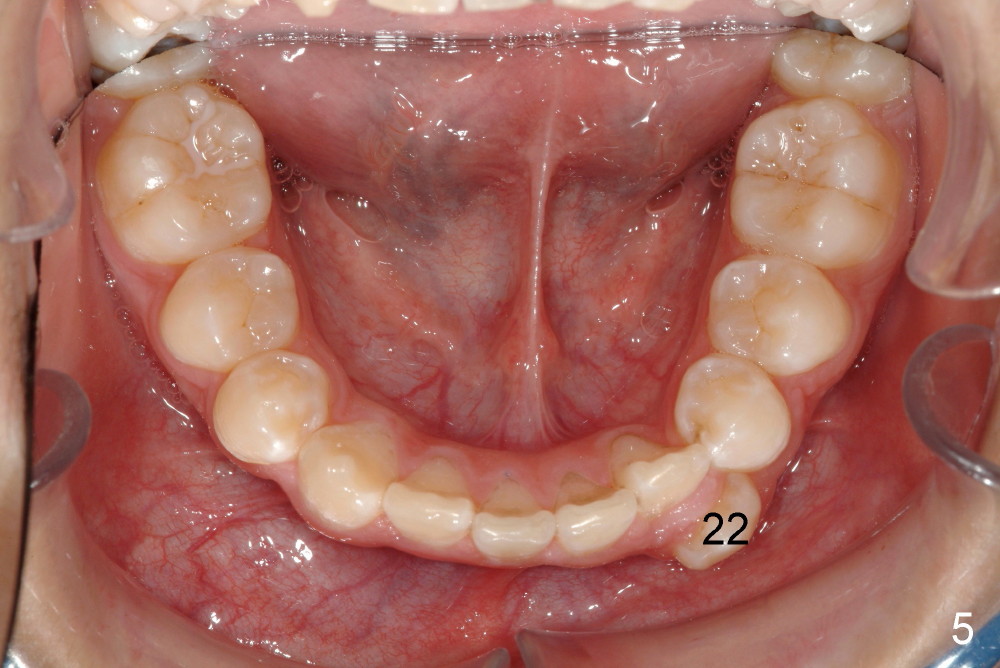

Please extract 5 and 12 in the maxilla, AND #22 in the mandible.  Yes, that is correct.  For a variety of reasons I am choosing to remove this tooth, i.e., mechanical advantage, less risk of bite opening, etc.  I also gave thought to extraction of #23 instead of #22 but the root length also points to the canine for extraction.  Bottom line, nothing made me NOT willing to extract #22, under these special circumstances.  Call me if you would like to discuss.

I hated to extract his lower left canine, more due to expected difficulty.  Amazingly, the patient was more ready for extraction than me.  He said that the tooth was not of use at all.  He has been under my care periodically for a while.  Her mom did not want to have treatment for his deciduous teeth.  Besides, he is my daughter's classmate.

In fact, the canine was easier to be extracted than the two upper first bicuspids.  It had been nonfunctional, out of occlusion.  The periodontal ligament must be loose and alveolar bone is immature.  The buccal bony plate is thin and low.  Toby returned for cleaning 3 days post extraction.  The three sockets healed so well that photos were taken.  Unfortunately the latter are misplaced.  Otherwise we would share them with you.

Was it hard to remove 22? The tissue in this area looked phenomenal. Very little evidence that it was there! You r good!!!